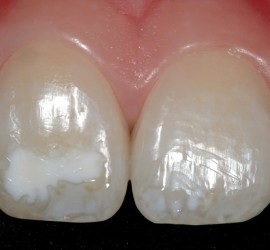

Лечение пульпита. При лечении пульпита перед врачом встают следующие задачи: избавление больного от болевых ощущений, ликвидация инфекционно-токсического очага в пульпе зуба, восстановление формы и функции зуба. Первую помощь больному острым пульпитом может оказать средний медработник или врач любого другого профиля. Она заключается в назначении внутрь обезболивающих препаратов типа анальгина, амидопирина, […]